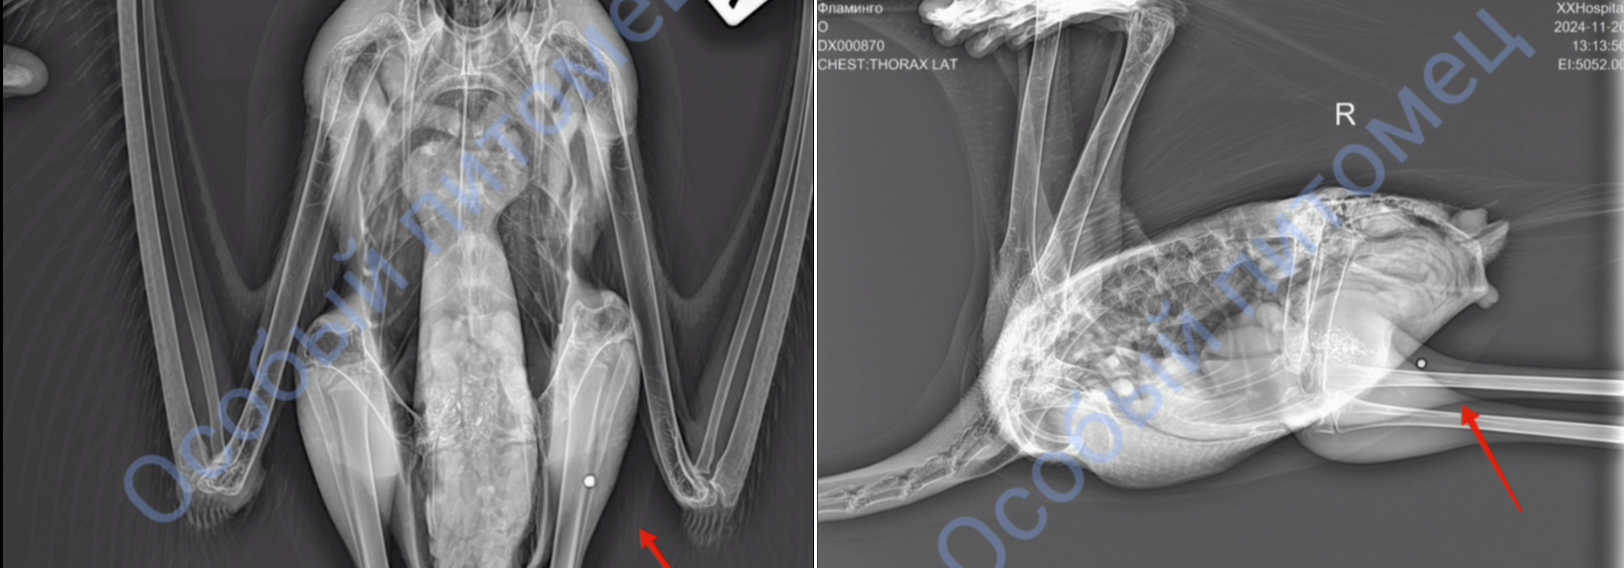

рентгеновский снимок. Фото: Центр «Особый питомец»

«В Кешу стреляли! За что? Чем провинились фламинго? Топчутся в своих болотцах и никого не трогают. <...> Одна из дробин застряла в мягких тканях лапы. Ее надо срочно удалять. Металл в теле Кеши каждую секунду отравляет его организм. Завтра прием врача. Ждем дату операции», — говорится в посте центра.